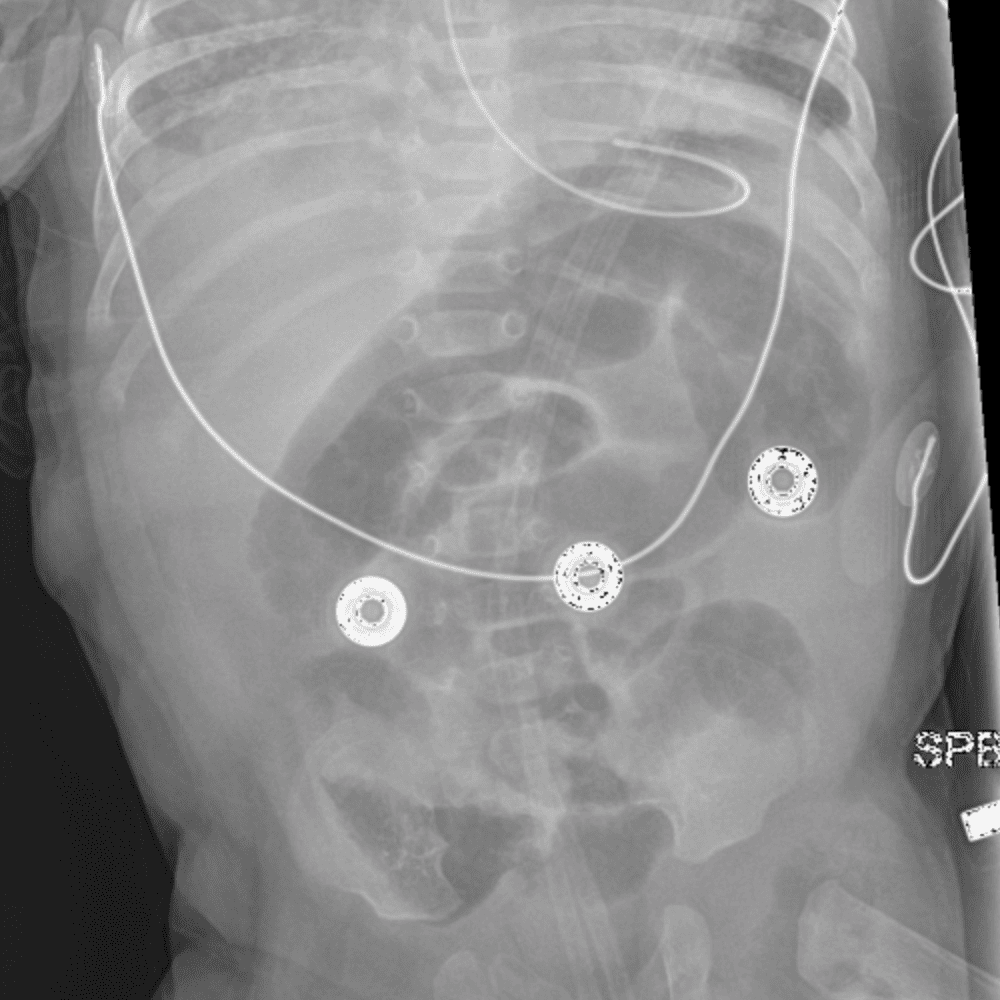

Peds Abdomen

Practice

Simulates call by including subtle or difficult cases and some normals.

30 cases